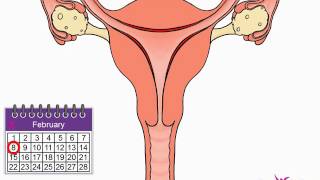

44. Animal Reproduction

Animal Reproduction

Menstrual Cycle (Mnemonic)